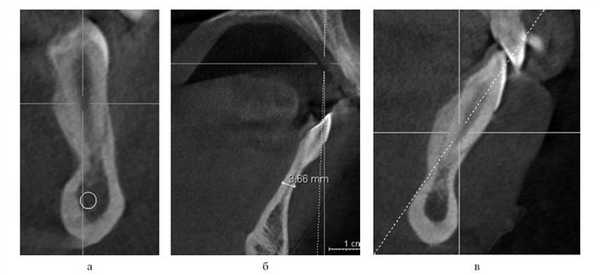

После прорезывания зубов форма альвеолярного отростка в поперечном срезе может напоминать песочные часы с сужением, расположенным между апексом корня и базисом челюсти (рис. 10). Рисунок 10. Форма альвеолярного отростка в виде «песочных часов». а — пациент М.Е.; б — пациент З.А.; в — пациент К.О.